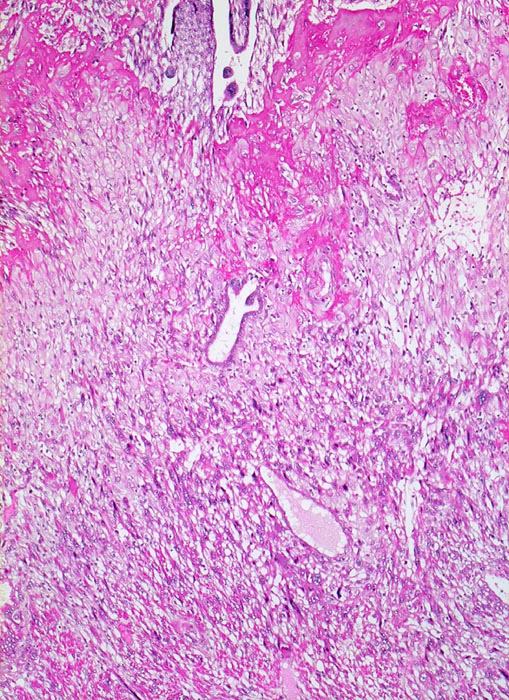

Basel 3BA FS/ Plazenta accreta

Plazenta accreta

Juxtaposition von Plazentarzotten und Myometrium durch Defekt der Dezidua und überschiessendes Einwachsen von Trophoblast.

In Abhängigkeit von Tiefe der Trophoblastinvasion Unterteilung in Plazenta accreta, increta und percreta.

• Plazenta accreta: Plazentarzotten haften dem Myometrium an ohne deziduale Zwischenschicht. Fibrin und Trophoblast kann vorhanden sein.

• Plazenta increta: Plazentaimplantation innerhalb des Myometriums.

• Plazenta percreta: Penetration der Plazentarzotten durch die gesamte Dicke des Myometriums hindurch.